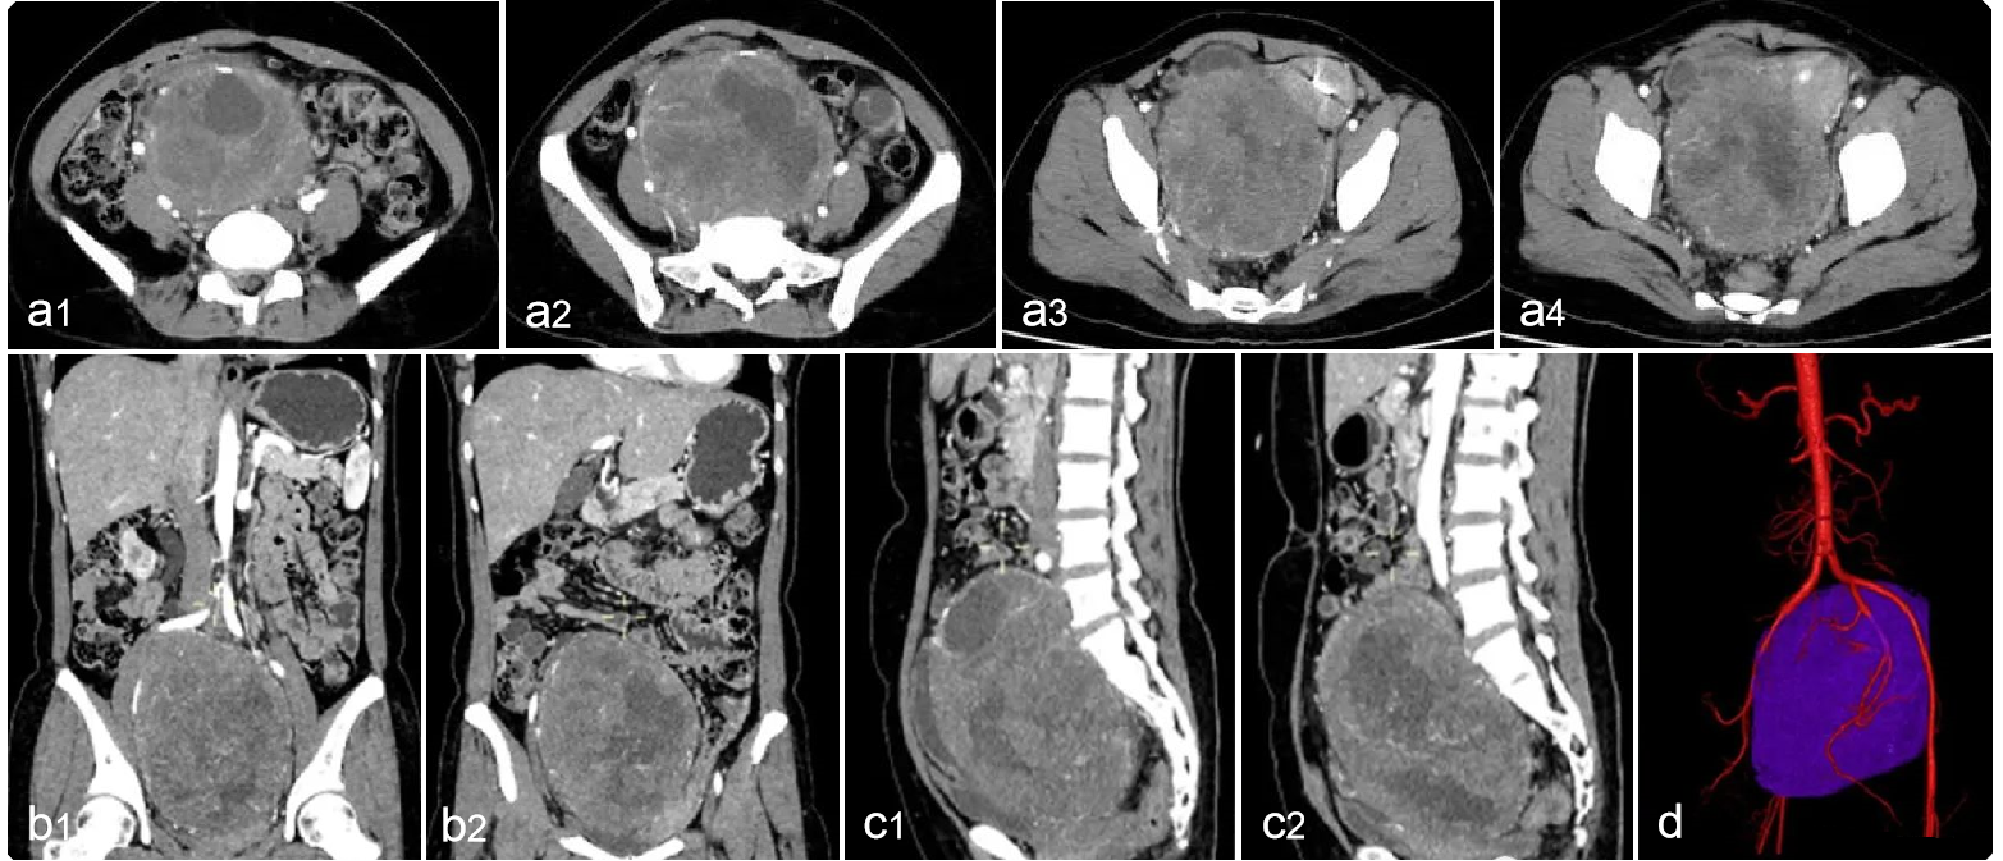

47df5e91be9763c0283a82cb0256446c.png 病例 23:(盆腔内)神经鞘瘤  46岁女性,因发现腹部肿块10余年,腹部隐痛1月余,实验室检查无特殊a1-a4为横断位多个层面;b1-b2为冠状位两个层面;c1-c2为矢状位两个层面;d为动脉和肿瘤的三维成像。肿瘤可见包膜,瘤体可见明显囊变坏死。免疫组化:S-100(+)、SOX-10(+)、CD117(-)、Dog-1(-)、 SMA(-)、Ki-67 (+,<1%)。特殊染色:PAS、网染无特殊。